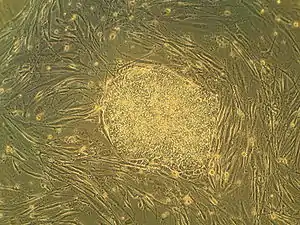

Embryonic stem cells (ES cells or ESCs) are pluripotent stem cells derived from the inner cell mass of a blastocyst, an early-stage pre-implantation embryo.[1][2] Human embryos reach the blastocyst stage 4–5 days post fertilization, at which time they consist of 50–150 cells. Isolating the embryoblast, or inner cell mass (ICM) results in destruction of the blastocyst, a process which raises ethical issues, including whether or not embryos at the pre-implantation stage should have the same moral considerations as embryos in the post-implantation stage of development.[3][4]

Embryonic stem cells (ESCs), derived from the blastocyst stage of early mammalian embryos, are distinguished by their ability to differentiate into any embryonic cell type and by their ability to self-renew. It is these traits that makes them valuable in the scientific and medical fields. ESCs have a normal karyotype, maintain high telomerase activity, and exhibit remarkable long-term proliferative potential.[7]

Embryonic stem cells of the inner cell mass are pluripotent, meaning they are able to differentiate to generate primitive ectoderm, which ultimately differentiates during gastrulation into all derivatives of the three primary germ layers: ectoderm, endoderm, and mesoderm. These germ layers generate each of the more than 220 cell types in the adult human body. When provided with the appropriate signals, ESCs initially form precursor cells that in subsequently differentiate into the desired cell types. Pluripotency distinguishes embryonic stem cells from adult stem cells, which are multipotent and can only produce a limited number of cell types.

Under defined conditions, embryonic stem cells are capable of self-renewing indefinitely in an undifferentiated state. Self-renewal conditions must prevent the cells from clumping and maintain an environment that supports an unspecialized state.[8] Typically this is done in the lab with media containing serum and leukemia inhibitory factor or serum-free media supplements with two inhibitory drugs ("2i"), the MEK inhibitor PD03259010 and GSK-3 inhibitor CHIR99021.[9]